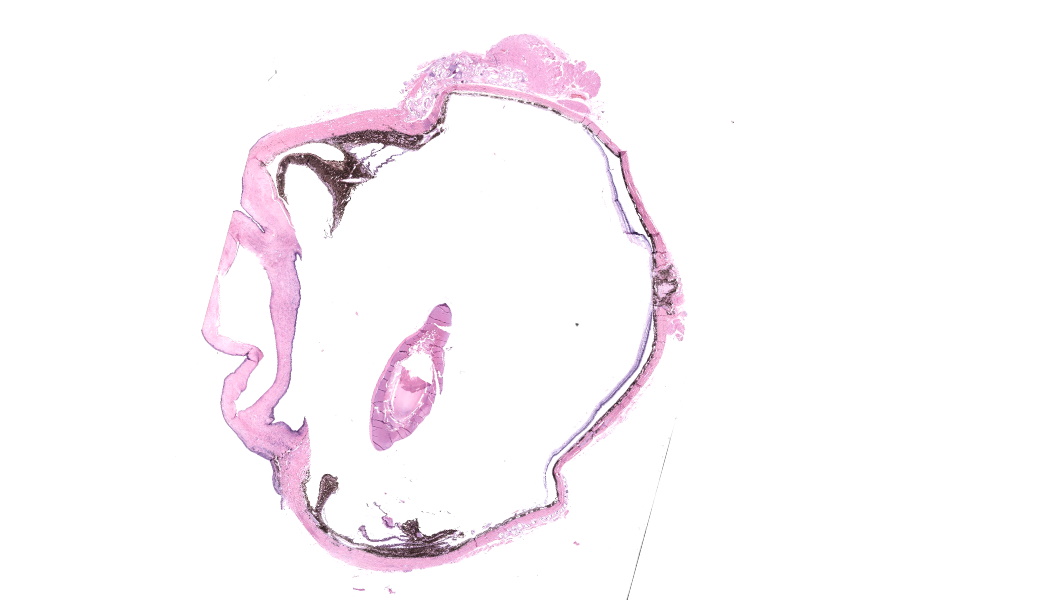

Enucleated right eye: Expanding and infiltrating the sclera, and occasionally extending to and dissecting the periocular skeletal muscle, are multiple cross and oblique sections of nematode parasites. Nematodes are characterized by a thick cuticle with annular ridges seen as raised areas in oblique sections, coelomyarian/polymyarian musculature that is atrophied and multifocally replaced by hypodermal tissue, a very small intestinal cross section, and reproductive organs. Mild hemorrhage, fibrin, and edema are present in affected sclera, and occasional nematode cross sections are surrounded by epithelioid macrophages. The cornea is hypercellular with low numbers of neutrophils and areas of neovascularization.Contributor's Morphologic Diagnoses:

- Globe and periocular tissue: Scleritis and orbital rhabdomyositis, granulomatous, chronic, multifocal, moderate, with adult filarids.